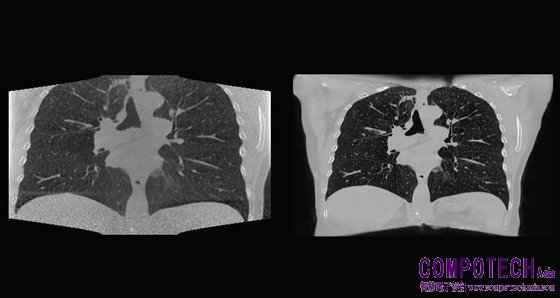

圖二_NKI 透過 AI 模型,重建出更好的錐狀射束電腦斷層掃描 (Cone Beam Computed Tomography;CBCT) 胸腔影像,與傳統方法相比,其影像畫質更清晰。

NKI 過去使用低解析度影像來訓練 AI 模型。由於 NVIDIA AI Enterprise 可提供更高的記憶體容量,該單位的研究人員可以改用高解析度的影像進行訓練,如此一來便有助於臨床醫生在病人每次接受治療時,更精準地鎖定腫瘤的大小和位置。

NKI 的研究人員使用運行在 HPE 組合式軟體系統 HPE Synergy 上的 NVIDIA AI Enterprise 來建立深度學習模型,結合巨量的 2D 及 3D 資料來源和 AI,在每次進行放射治療前精準地鎖定腫瘤位置。

荷蘭癌症研究所腫瘤學人工智慧小組負責人 Jonas Teuwen 表示:「醫生可以在治療當天使用該解決方案來取代電腦斷層掃描 (CT),藉以最佳化治療方案,並驗證放療計畫。」

Teuwen 在阿姆斯特丹的團隊使用 NVIDIA AI Enterprise,在位於矽谷的伺服器中的 NVIDIA A100 80GB GPU 上運行 AI 作業負載,並在不到三個月的時間建立一個卷積神經網路,又使用不到 300 個臨床肺部 CT 掃描資料進行訓練,接著進行重建並推論到頭部和頸部資料。